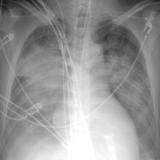

APE IABP

Date: 10/17/2010

Views: 3835